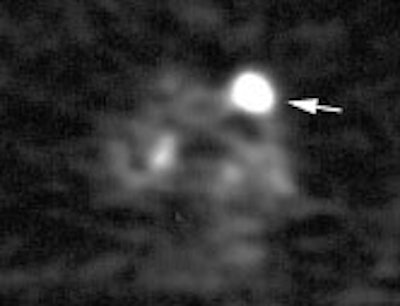

Example: This patient with a left lung non-small cell lung cancer demonstrated a pathologic aorto-pulmonary window node (N2) by CT size criteria (white arrow), and a non-pathologic retrocaval-pretracheal contralateral mediastinal node (N3) (yellow arrow). PET-FDG images revealed increased tracer accumulation within both nodes, consistent with metastases. (Case courtesy of H. Page McAdams MD, Department of Radiology, Duke University Medical Center)